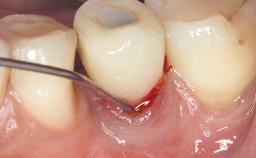

In this case, Myroslav Solonko, Ignacio Sanz Sánchez and Mariano Sanz present a treatment that aims to eliminate exposed implant threads by modifying the implant surface, converting a moderately-rough surface into a smooth surface.